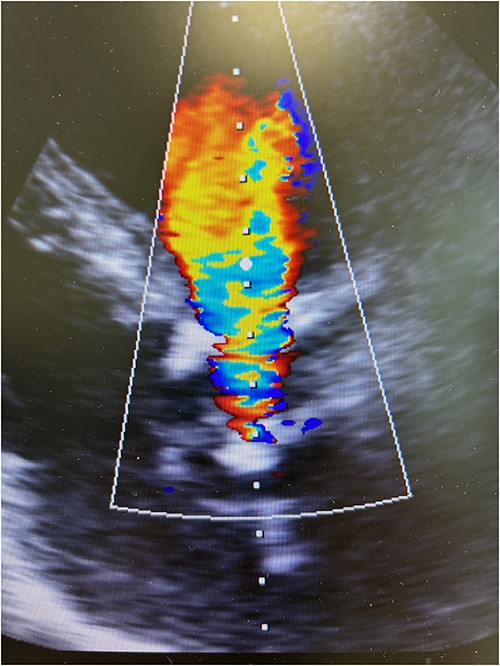

The patient experienced significant dyspnea, increased passiveness, decreased performance, and cardiac echocardiography revealed a destroyed, regurgitant, and stenotic aortic valve prosthesis with myocardial calcification of the left outflow track (Fig. 1) including a peak mean aortic gradient of 76/49 mmHg, Vmax 4.3 m/s and AVA 1.0 cm2 and significant regurgitation (Fig. 2). Minimal mitral valve regurgitation and some coronary artery stenosis were also present.

Preoperative transesophageal echocardiography showing significant regurgitation and stenosis of the aortic valve bioprosthesis.

Resternotomy was undertaken and the aortic root was dissected free of considerable adhesions. The aortic arch and the remnant of the right atrial appendix were cannulated to initiate cardiopulmonary bypass and retrograde cardioplegia was administered after cross-clamping of the aortic prosthesis, which was thereafter transected immediately distally to the previous proximal aortic suture line. Care was applied while the destroyed aortic valve prosthesis and the coronary ostia were dissected free from the left outflow track encompassing the calcified annular structure, pledgets, and suture material. Though the aortic root remained intact after surgical revision, the remnant aortic valve annulus was torn and an intramyocardial defect was evident beneath the left and right coronary ostia. A size 23 mm rapid-deployment Edwards Intuity bioprosthesis was implanted with the aid of three guiding sutures that also ensured the integrity of the coronary ostia. The skirt of the prosthesis was raised up and the aortic valve prosthesis was well fit despite the revision lesions and intramyocardial calcium of the left outflow track beneath the old aortic valve annulus. After surgical closure of the supracoronary aortic prosthesis and weaning from cardiopulmonary bypass, echocardiography revealed a well-seated aortic valve prosthesis with a trace of paravalvular leak (Fig. 3). The patient experienced minimal weakness of the left arm during an otherwise uneventful recovery without cerebral lesions observed by computed tomography. Clopidrogel was readministered and the patient was dehospitalized after 10 days of surgery.

Postoperative transesophageal echocardiography showing nonsignificant regurgitation of a well-seated rapid-deployment Edwards Intuity bioprosthesis.